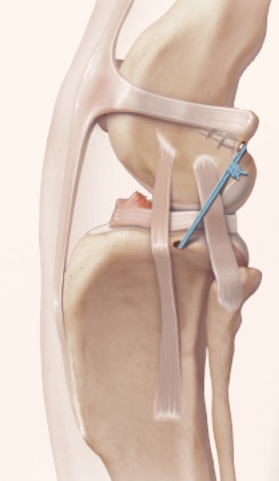

Extra-Capsular Stabilization - additional information

Post Surgical Radiographs

While the patient is still anesthetized, the patient is taken into radiology for post-surgery radiographs (X-rays). The radiographs are assessed to ensure the apparatus FASTak screw and toggle are appropriately positioned.